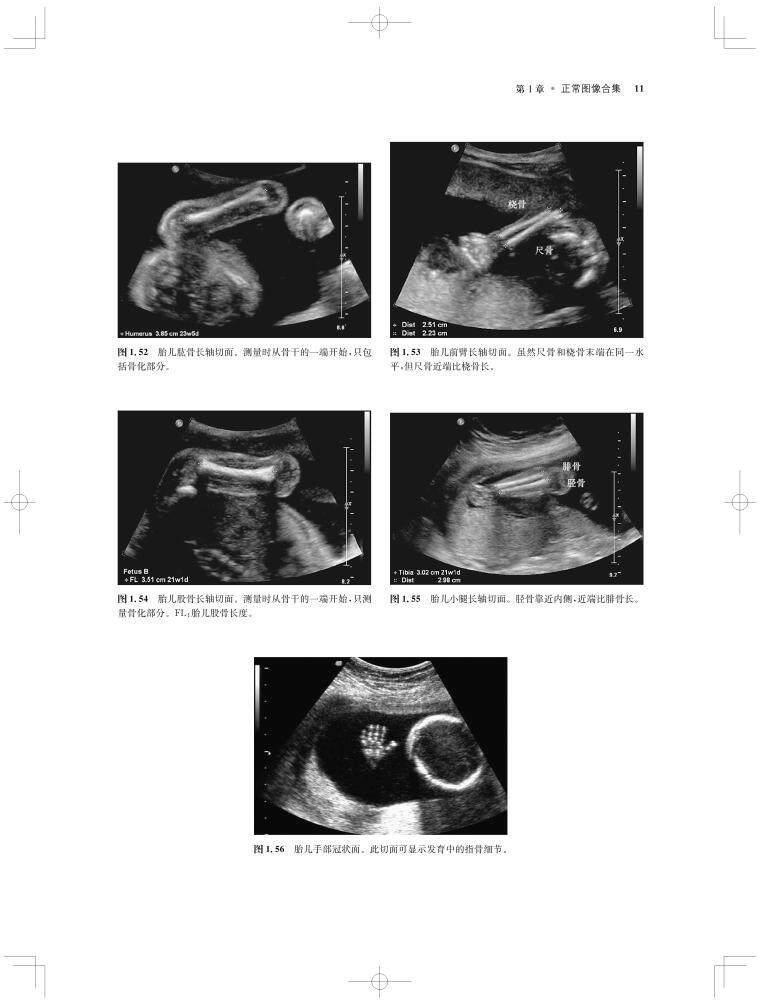

内容涵盖了胎儿宫内疾病的所有病种,从疾病的概述、流行病学、病因学、病理生理学,到临床表现、各类影像学技术的诊断和鉴别诊断,再到产前、产后的治疗和干预手段,都做了全面介绍,重点阐述了疾病的超声、X线、CT、MRI、PET、CT等影像学表现,以及诊断与鉴别诊断,并辅以大量标准化的影像学图片,图文并茂。

《产科影像学——胎儿诊断和监护》是Elsevier(Saunders)出版的“Expert Series”之一,由国际最顶尖的妇产科、生殖科、母胎医学和影像学专家共同编写,代表着该领域最顶尖的水平。书中配有大量典型影像图片,内容丰富全面,编写理念先进,侧重于疾病的影像学征象分析及鉴别诊断和诊断流程的制定,从临床思维上进行了更新;同时兼顾临床和病理医师,重点内容以列表、提要、要点的形式进行总结,提纲挈领,方便读者阅读、记忆。对于每天不断进行诊断与鉴别胎儿疾病的影像工作者、病理科和临床医师而言,具有重要的参考价值。